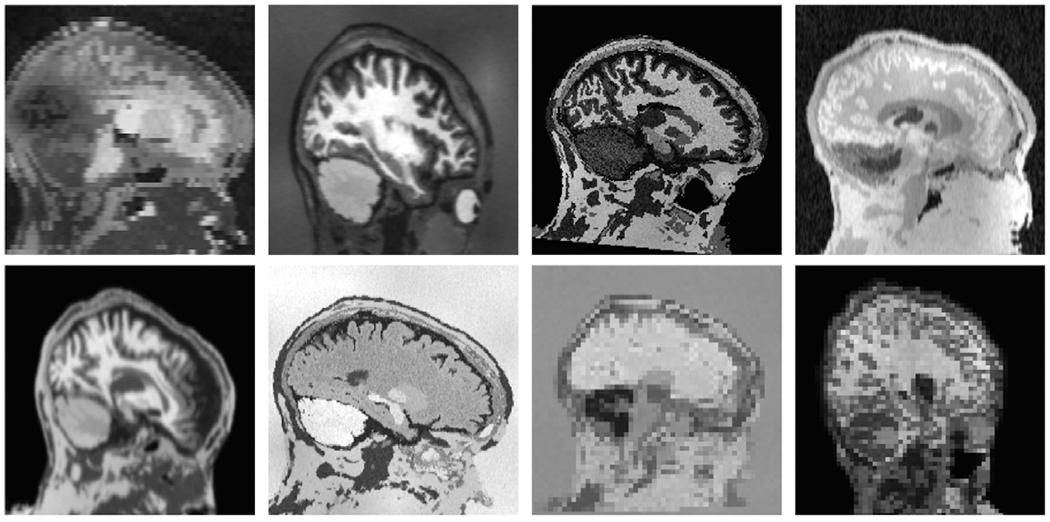

The removal of non-brain signal from magnetic resonance imaging (MRI) data, known as skull-stripping, is an integral component of many neuroimage analysis streams. Despite their abundance, popular classical skull-stripping methods are usually tailored to images with specific acquisition properties, namely near-isotropic resolution and T1-weighted (T1w) MRI contrast, which are prevalent in research settings. As a result, existing tools tend to adapt poorly to other image types, such as stacks of thick slices acquired with fast spin-echo (FSE) MRI that are common in the clinic. While learning-based approaches for brain extraction have gained traction in recent years, these methods face a similar burden, as they are only effective for image types seen during the training procedure. To achieve robust skull-stripping across a landscape of imaging protocols, we introduce SynthStrip, a rapid, learning-based brain-extraction tool. By leveraging anatomical segmentations to generate an entirely synthetic training dataset with anatomies, intensity distributions, and artifacts that far exceed the realistic range of medical images, SynthStrip learns to successfully generalize to a variety of real acquired brain images, removing the need for training data with target contrasts. We demonstrate the efficacy of SynthStrip for a diverse set of image acquisitions and resolutions across subject populations, ranging from newborn to adult. We show substantial improvements in accuracy over popular skull-stripping baselines - all with a single trained model. Our method and labeled evaluation data are available at https://w3id.org/synthstrip.

从磁共振成像 (MRI) 数据中去除非脑信号,即头骨剥离,是许多神经影像分析流程的一个组成部分。尽管它们很丰富,但流行的经典头骨剥离方法通常针对具有特定采集属性的图像进行定制,即近各向同性分辨率和 T1 加权 (T1w) MRI 对比,这些属性在研究环境中很常见。因此,现有的工具往往难以适应其他类型的图像,例如在临床上常见的快速自旋回波 (FSE) MRI 采集的厚切片堆栈。虽然近年来基于学习的脑提取方法已经引起了关注,但这些方法面临着类似的负担,因为它们仅对训练过程中看到的图像类型有效。为了在成像协议的广阔领域中实现稳健的头骨剥离,我们引入了 SynthStrip,这是一种快速的、基于学习的脑提取工具。通过利用解剖分割来生成一个完全合成的训练数据集,其中包含解剖结构、强度分布和伪影,远远超出了医学图像的实际范围,SynthStrip 学会了成功地推广到各种真实采集的脑图像,而无需具有目标对比的训练数据。我们展示了 SynthStrip 在不同的图像采集和分辨率下对不同人群的有效性,从新生儿到成年人都有涉及。与流行的头骨剥离基线相比,我们的方法在准确性上有了显著提高 - 所有这些都只需要一个训练好的模型。我们的方法和标记评估数据可在 https://w3id.org/synthstrip 上获得。